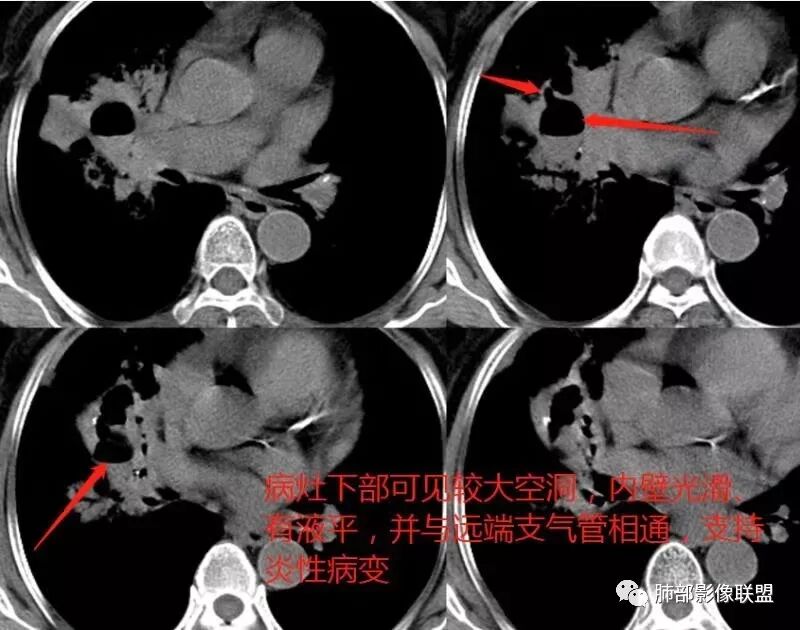

胸CT:右肺上叶实变内可见支气管充气征,近端支气管狭窄,远端扩张,周围可见毛玻璃影,右肺中叶支气管闭塞,并可见气道壁钙化,右肺中叶体积缩小,实变内可见空洞,并可见气液平面,空洞周围可见毛玻璃样影,右肺下叶支气管开口狭窄,右肺门淋巴结肿大。纵隔窗可见病灶与壁层胸膜间隙增宽,考虑良性病变-----感染性病变------TB?

ggo边界清,远端支气管狭窄,常规考虑肺炎型肺癌;但这个空洞内壁光滑。

老年女性,慢性病程,咳嗽伴白色粘液痰,无发热腹痛,糖尿病,白细胞及C反应蛋白不高,血沉快,铁蛋白高。胸部CT,右肺上叶大片状实变伴磨玻璃密度影,边界不清,边缘局部膨隆,叶裂弧形下坠,实变影宽基底与胸膜相贴;右肺下叶前基底段见类似病灶;右肺中叶不张并空洞形成,空洞内见气液平面;综合考虑右肺上叶及下叶肺炎型肺癌,右肺中叶结核。

老年女性,亚急性起病,右肺上中叶大片状影,跨叶,上叶为主,磨玻璃为主,边界模糊,部分实变,内见空洞影和液气平面,壁光滑,洞内可见结节形成,局部有扩张,首先考虑感染性病变,结核可能;洞内可见结节样病灶,鉴别合并曲霉、肿瘤。

1.王老师的病理说明粘液腺癌的破坏力弱,对血管和支气管破坏少,所以理论上空洞少,这个空洞很明确。

2.南大理论:粘液腺癌起源于外周,所以主体病灶位于胸膜下多见,这个病人主体病灶位于中心,外周磨玻璃为主,部分磨玻璃模糊

3.熊老师告诉我们:肺结核可以有磨玻璃,这个我以前一直不知道,右肺门淋巴结有钙化,病灶内纵膈窗隐约细细点状钙化,所以结核磨玻璃可以,

这个病人可以当做干酪性肺炎的扩大延长版